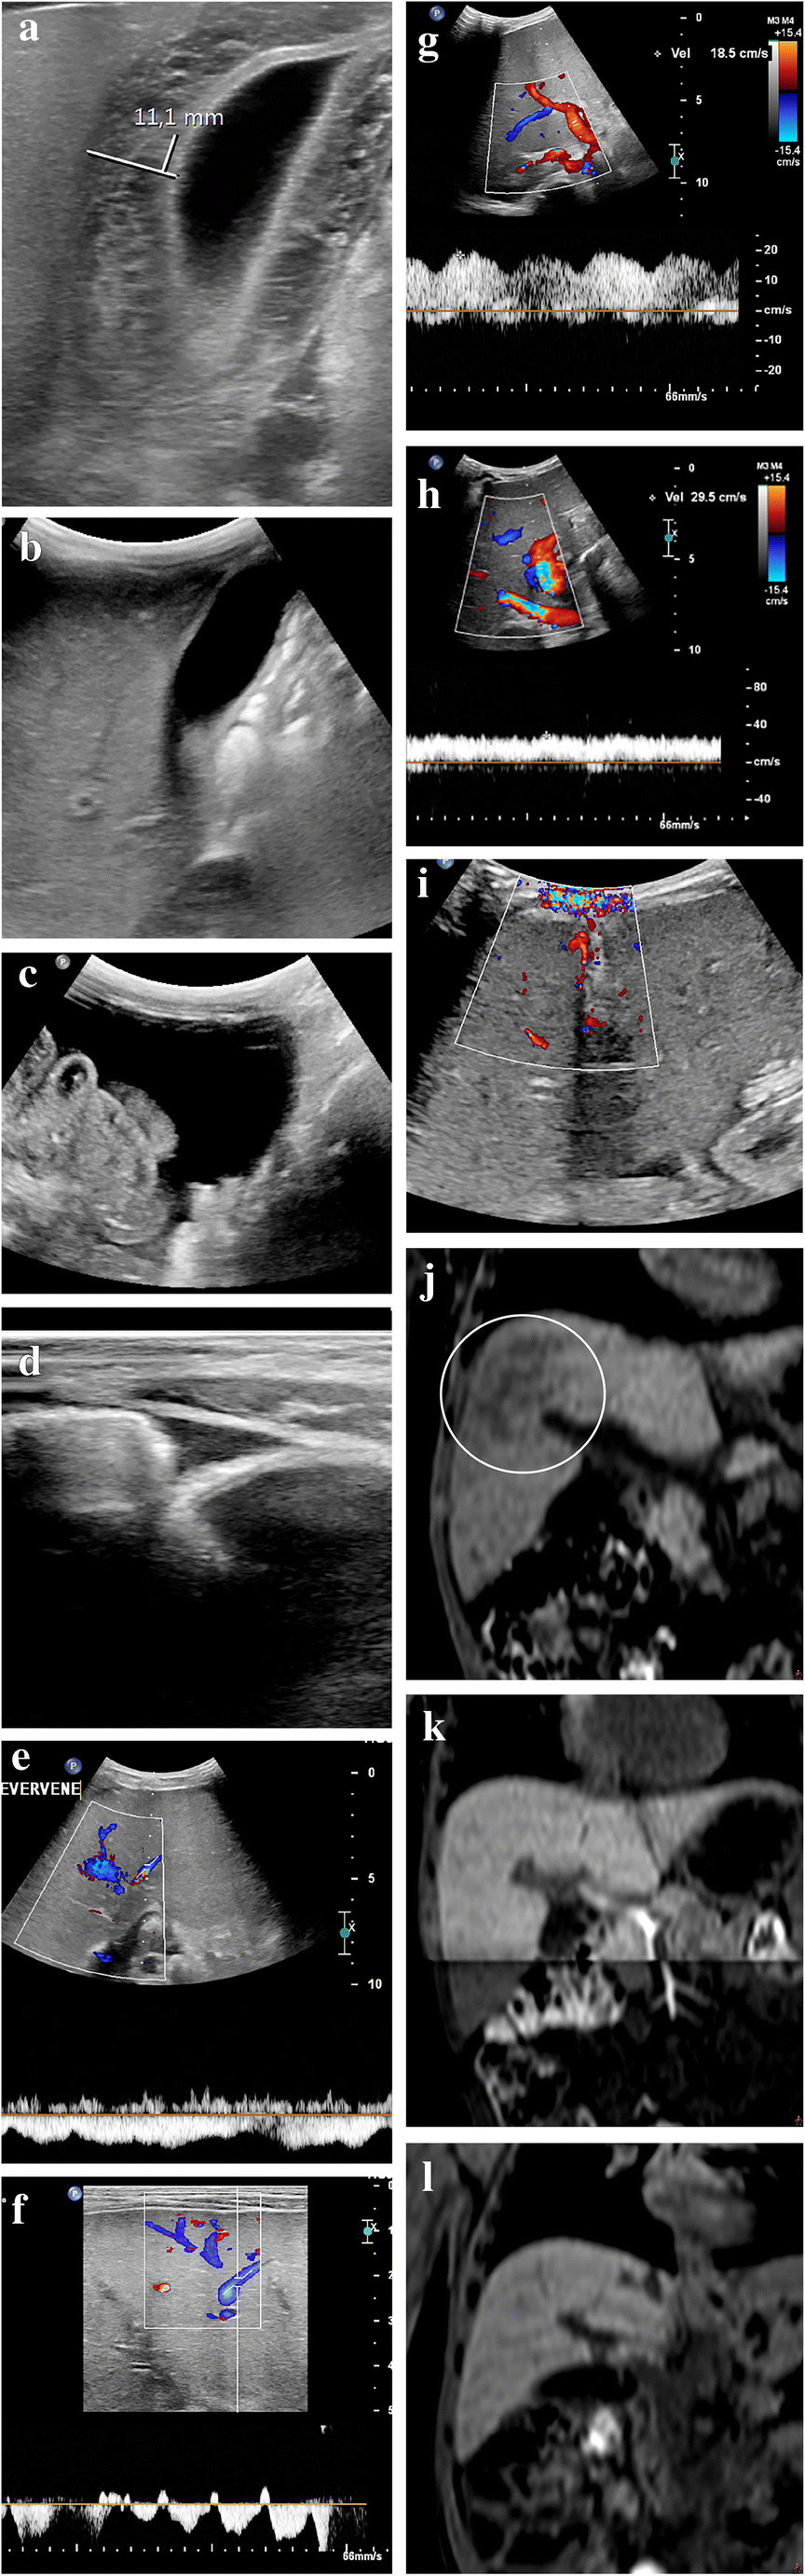

Fig. 3

Ultrasound (US) findings of severe sinusoidal obstruction syndrome including follow-up in a 2-year-old boy with neuroblastoma after a high dose of busulfan/melphalan and autologous stem cell transplantation. Ten days after stem cell reinfusion he developed a fever, increasing belly circumference and weight gain. Clinical and laboratory parameters initially indicated moderate sinusoidal obstruction syndrome. A few days later, clinical and imaging findings indicated severe sinusoidal obstruction syndrome. The patient was treated successfully with fluid restriction, diuretics and defibrotide. a, b Transverse gray-scale US images show initial gallbladder wall edema of 11 mm (a), which resolved 3 weeks later (b). c, d Transverse gray-scale US images in the lower abdomen show moderate ascites (c), which diminished on follow-up (d). e An axial intercostal US color Doppler image shows the absence of normal triphasic hepatic venous outflow pattern as a result of congestion-related loss of liver compliance. f An axial intercostal color Doppler US image shows how the normal hepatic vein flow pattern was restored on follow-up. g An axial intercostal color Doppler US image shows initial increased pulsatility of the portal vein. h An axial intercostal color Doppler US image shows how this improved on follow-up. i A transverse US color Doppler image shows collateral blood flow along the falciform ligament and in the paraumbilical veins (no follow-up image available). j A coronal reformatted non-contrast-enhanced three-dimensional (3-D) T1-weighted fast field echo magnetic resonance (MR) image (repetition time/echo time 5.89/0 ms) performed 4 weeks after the start of sinusoidal obstruction syndrome treatment shows slight heterogeneity of the liver (circle). k This was not visible several months earlier on coronal reformatted non-contrast-enhanced 3-D T1-weighted fast field echo MRI. l The heterogeneity resolved several months later on coronal reformatted non-contrast-enhanced 3-D T1-weighted fast field echo MRI. No elastography measurements were performed